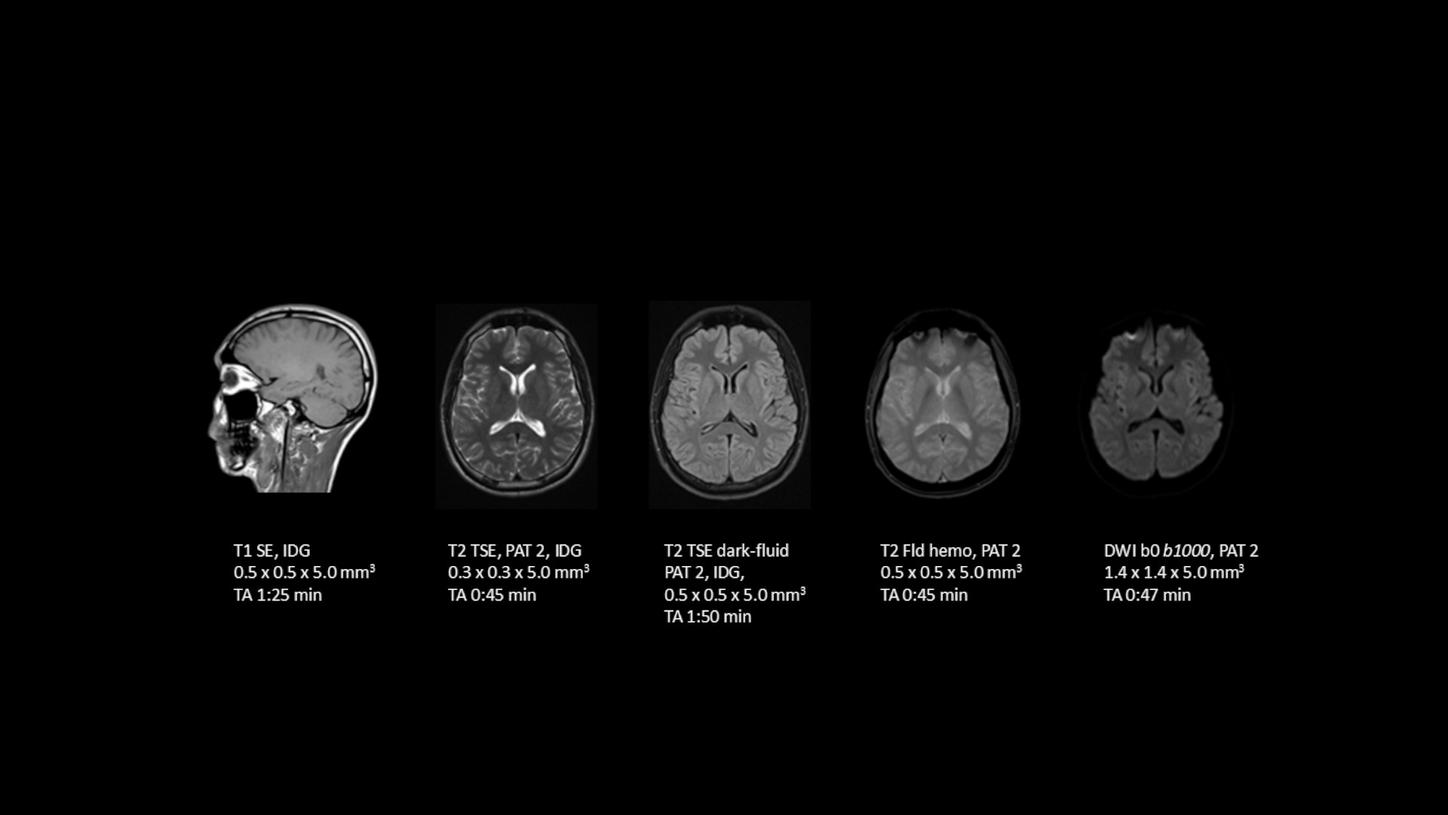

Deep Resolve is at the forefront of the revolution in MRI acceleration. Deep Resolve delivers our fastest MRI, delivering images of extraordinary clarity, higher clinical productivity, and a better patient experience.